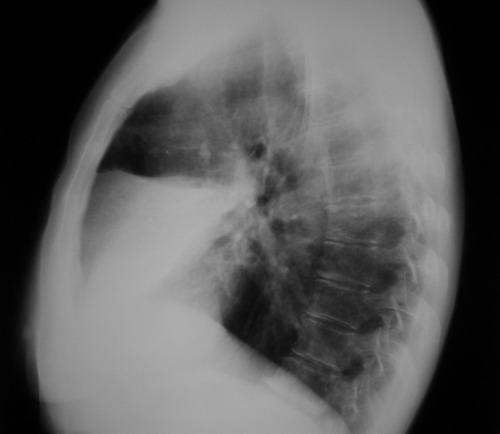

标题: 回复:[原创]右侧位

右中叶实变,侧位片示右上、下叶见斑点状阴影,结合病史,如是大叶性肺炎,应有发热。患者咳血,年龄较大,应警惕肿瘤,可是右肺门未见明显增大,周围见斑点影,还是先考虑结核。建议进一步纤支镜检查。

右中叶大叶性肺炎(右肺中叶实变,体积未见明显变化-叶间裂未见明显移位)请结合临床症状体征进一步分析;(咳血并非为结核或肺癌所特有)

右中肺野示一片状高密度影,上缘较清。侧位呈三角形,尖端指向肺门。考虑:右肺癌可能性大。

中间段支气管存在,肺体积未见明显缩小,所以应考虑右中叶大叶性肺炎。